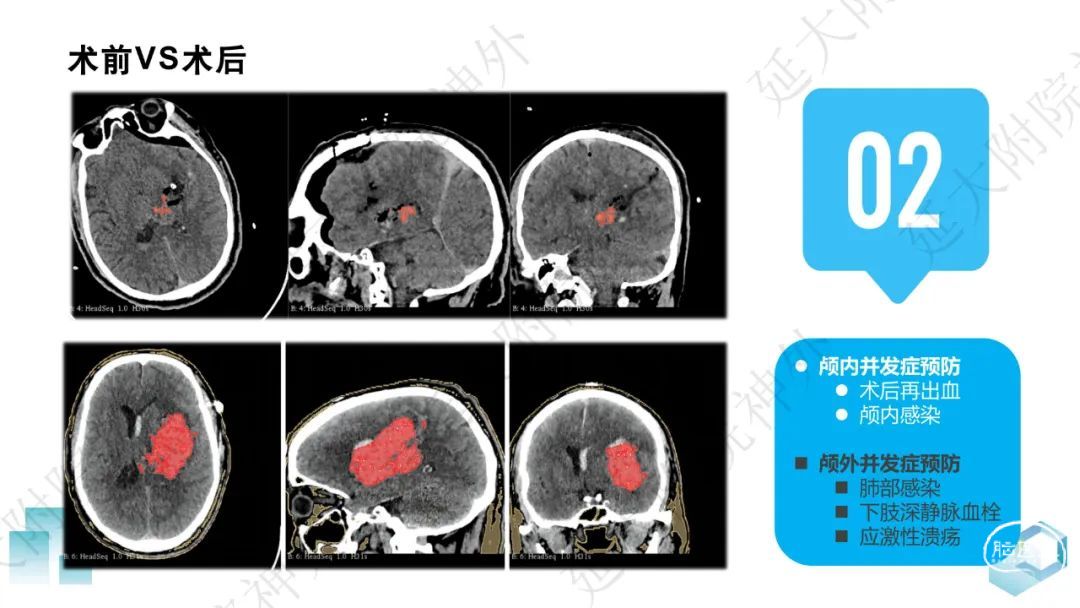

今天为大家分享的是《监测有道丨颅脑创伤-神经重症周刊》第332期,由延安大学附属医院神经外科贾云峰主任医师带来的:左侧基底节区出血破入脑室一例神经内镜下血肿清除术,欢迎阅读、分享。

长期从事神经外科疾病的基础与临床研究。专长于神经急危重症综合治疗、神经内镜脑出血微创手术、脊髓脊柱疾病显微外科微创治疗、颅内及脊髓肿瘤、脑血管病、脑、脊髓先天畸形的微创治疗。参与主持完成科研项目《尼莫地平对脊髓损伤的作用研究》等,获陕西省自然科学优秀论文奖。参与国家卫健委牵头的《自发性脑出血的多中心登记研究》等项目研究及《脑出血患者颅内压监测》《脑出血后脑水肿的治疗》专家共识的制定。以第一作者在国内外发表核心期刊20余篇,SCI收录文章1篇,多次应邀在中华医学会、中国医师协会全国神经外科学年会交流发言。主编及参编著作3部,国家发明专利2项